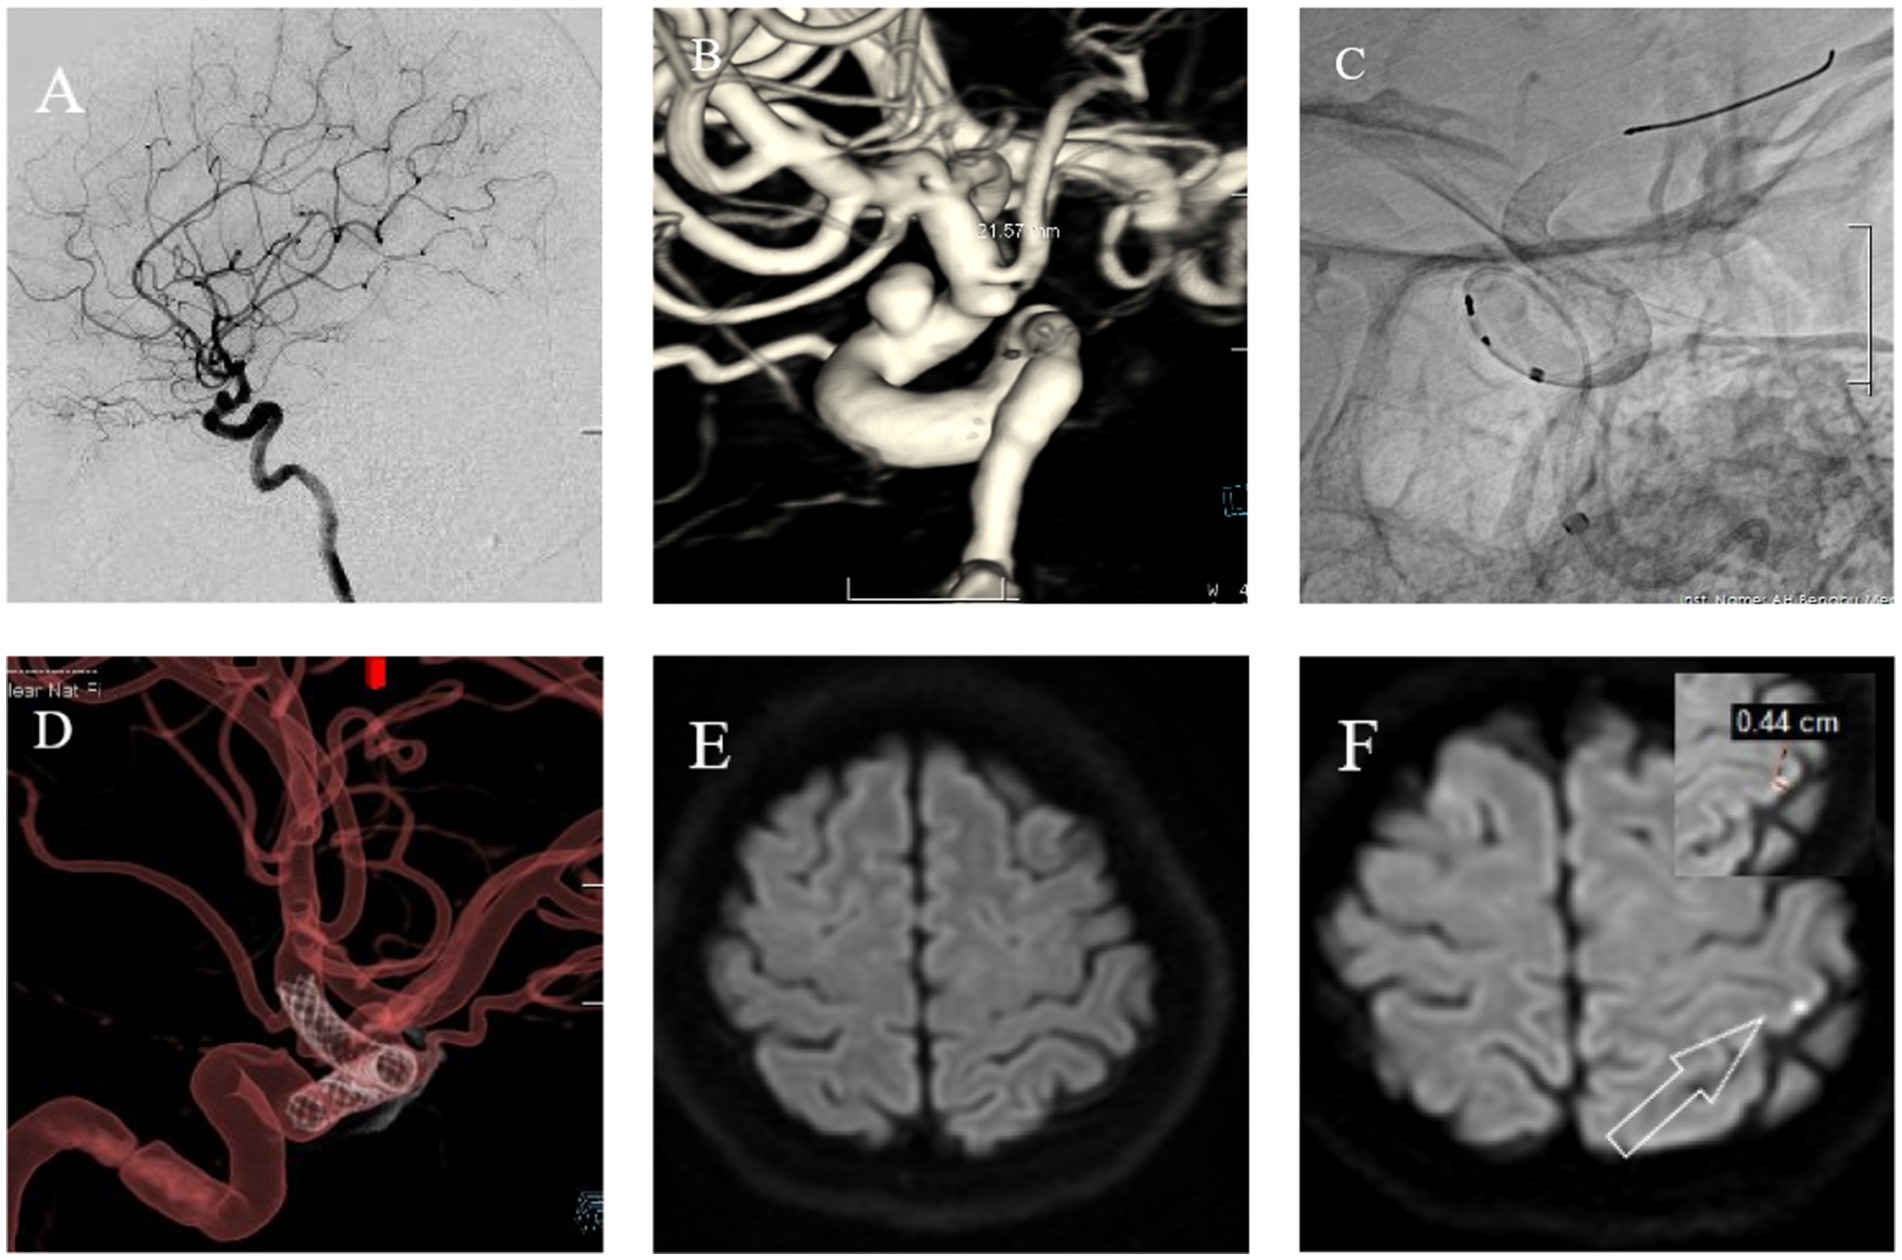

The following brief descriptions of cases of postoperative microembolic infarction are based on clinical treatment and imaging data, as shown in Figures 3, 4.

Figure 4

Female, 56 years old. Intermittent headaches for over 7 months, worsening for 1 week. (A) Cranial DSA showing the location of the intracranial aneurysm in the 2D plane during the operation. (B) Cranial DSA showing the location of the aneurysm in the 3D image, confirming it is in the ophthalmic artery segment of the left internal carotid artery. (C) Intraoperative 2D plane showing the location of the stent. (D) Postoperative 3D plane showing the stent model. (E) Preoperative MRI-DWI showed no new infarcts. (F) Postoperative day 3 MRI-DWI showed an acute microinfarction lesion in the left parietal lobe with a diameter of approximately 0.44 cm.